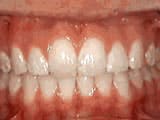

Open bite: front teeth don’t touch

Before

AfterThis girl sucked her thumb as a young child. She started treatment at age 13. She had braces and a special appliance — called a crib — to retrain the tongue, for 28 months. Now she can bite the lettuce out of a sandwich.